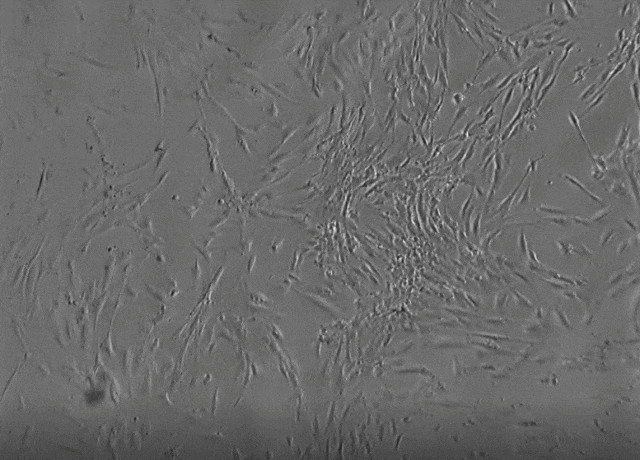

柳叶刀旗下杂志 《Eclinical Medicine》的一篇文章,总结了2012年至2019年的间充质干细胞临床随机试验,结果一如既往的证实了间充质干细胞的安全性。

与MSC治疗相关的不良事件。这次的研究也再次增加了47项随机临床研究(从4914个研究中筛选出来),共计有55个随机临床的研究,包含了2696例病人,是之前研究的升级版。在研究之中有心血管疾病、神经系统疾病、肾脏疾病、肝脏疾病、呼吸系统疾病、内分泌疾病、血液/肿瘤恶性肿瘤、免疫缺陷或炎症疾病状态的。细胞来源包括了骨髓、脐带、脂肪等。在经过了综合的分析,MSC组发热的风险显著高于对照组(但较2012年总结时有所降低),MSC组表现出发生血栓/血栓栓塞事件的风险与对照组相比没有显著的增加,MSC组死亡风险明显要低于对照组,与对照组相比较的情况下,MSC组发生恶性肿瘤或者异位组织形成风险无明显的增加。在亚组分析中,MSC组在神经与免疫/炎症的人群当中,回输异体骨髓、脐带或者新鲜MSCs,以及MSC培养基为非人源(或不清楚)的时候,急性的输血毒性风险增加。MSC组在三组临床人群(心血管疾病、神经系统疾病和肝病)中死亡的风险有明显降低。最后认为:MSC治疗与无发热急性输注毒性、感染或者恶性肿瘤发展之间没有任何的联系,也没有发现MSC治疗与血栓的发展之间的联系。但MSC治疗与发烧依然有较大的联系,在19个随机临床的试验当中,总计有880例报告发烧的患者,只有6例报告病情严重。审查结果可以为研究人员、临床医生、监管者、病人和家属提供额外的保证,即MSCs的使用是安全可靠的。文章也提出了,随着间充质干细胞来源的多样性(譬如胚胎或者IPS)以及新的二代间充质干细胞,研究还在继续。最近体外与临床数据的发现,MSCs可以表达或者增加与凝血相关的蛋白质(例如组织因子、凝血酶抗凝血酶复合物)与血栓形成的报道。根据临床的不同,潜在的促凝作用可能会导致有益或有害的临床效应。本篇的文章之中,也纳入了血栓事件作为预先规定的不良事件,研究没有发现重大的关联,这些事件很可能也是罕见的,因此鼓励研究人员未来能够积极监测与报告有关方面的不良事件。

最新的一篇发表在《Stem Cell Research&Therapy》 的荟萃分析,回顾了过去15年的间充质干细胞临床试验,确定了间充质干细胞给药相关的所有治疗相关不良事件,并探讨间充质干细胞在临床应用中的安全性,结论显示:长达15年,3546名患者,62项临床研究结果证实间充质干细胞临床安全!所有研究中只有2项研究是前瞻性的非随机试验,其余的是随机对照试验(RCT),范围从临床试验1/2期到3期。其中临床试验数量亚洲排名

,研究数量最多。其次是北美和欧洲。这些研究中使用的间充质干细胞主要分离自骨髓、脂肪组织和脐带。注射剂量范围为4×10^7到1.2×10^9细胞。随访时间从6个月到2年。发现MSC给药与主要不良事件没有密切关系,如血管疾病,荨麻疹/皮炎,中枢神经系统疾病,腹泻,死亡或感染。分析表明,MSC治疗可能会引起患者48小时内可能出现短暂发热。同时,MSC注射也可能在给药部位引起不良事件。关于其他轻微不良事件,间充质干细胞可能与失眠相关,便秘和疲劳相关。而与贫血、代谢和营养障碍、恶心、癫痫发作和呕吐则无关。总之,现已完成的多项临床研究证实MSC给药与短暂发热和给药部位不良事件有很强的相关性,与其他不良反应无关。随着技术的不断进步,干细胞的安全性得到了极大的保障。研究表明,在一定的条件下,干细胞的诱导分化可以被有效控制,从而避免肿瘤形成的风险。同时,通过使用免疫抑制剂等方法,可以降低干细胞移植后的免疫排斥反应。免责声明:内容来源于网络,版权归原作者所有。本文为科普性知识,仅作信息交流之目的,不做商业用途,如涉及作品内容、版权和其它问题,请联系我们删除